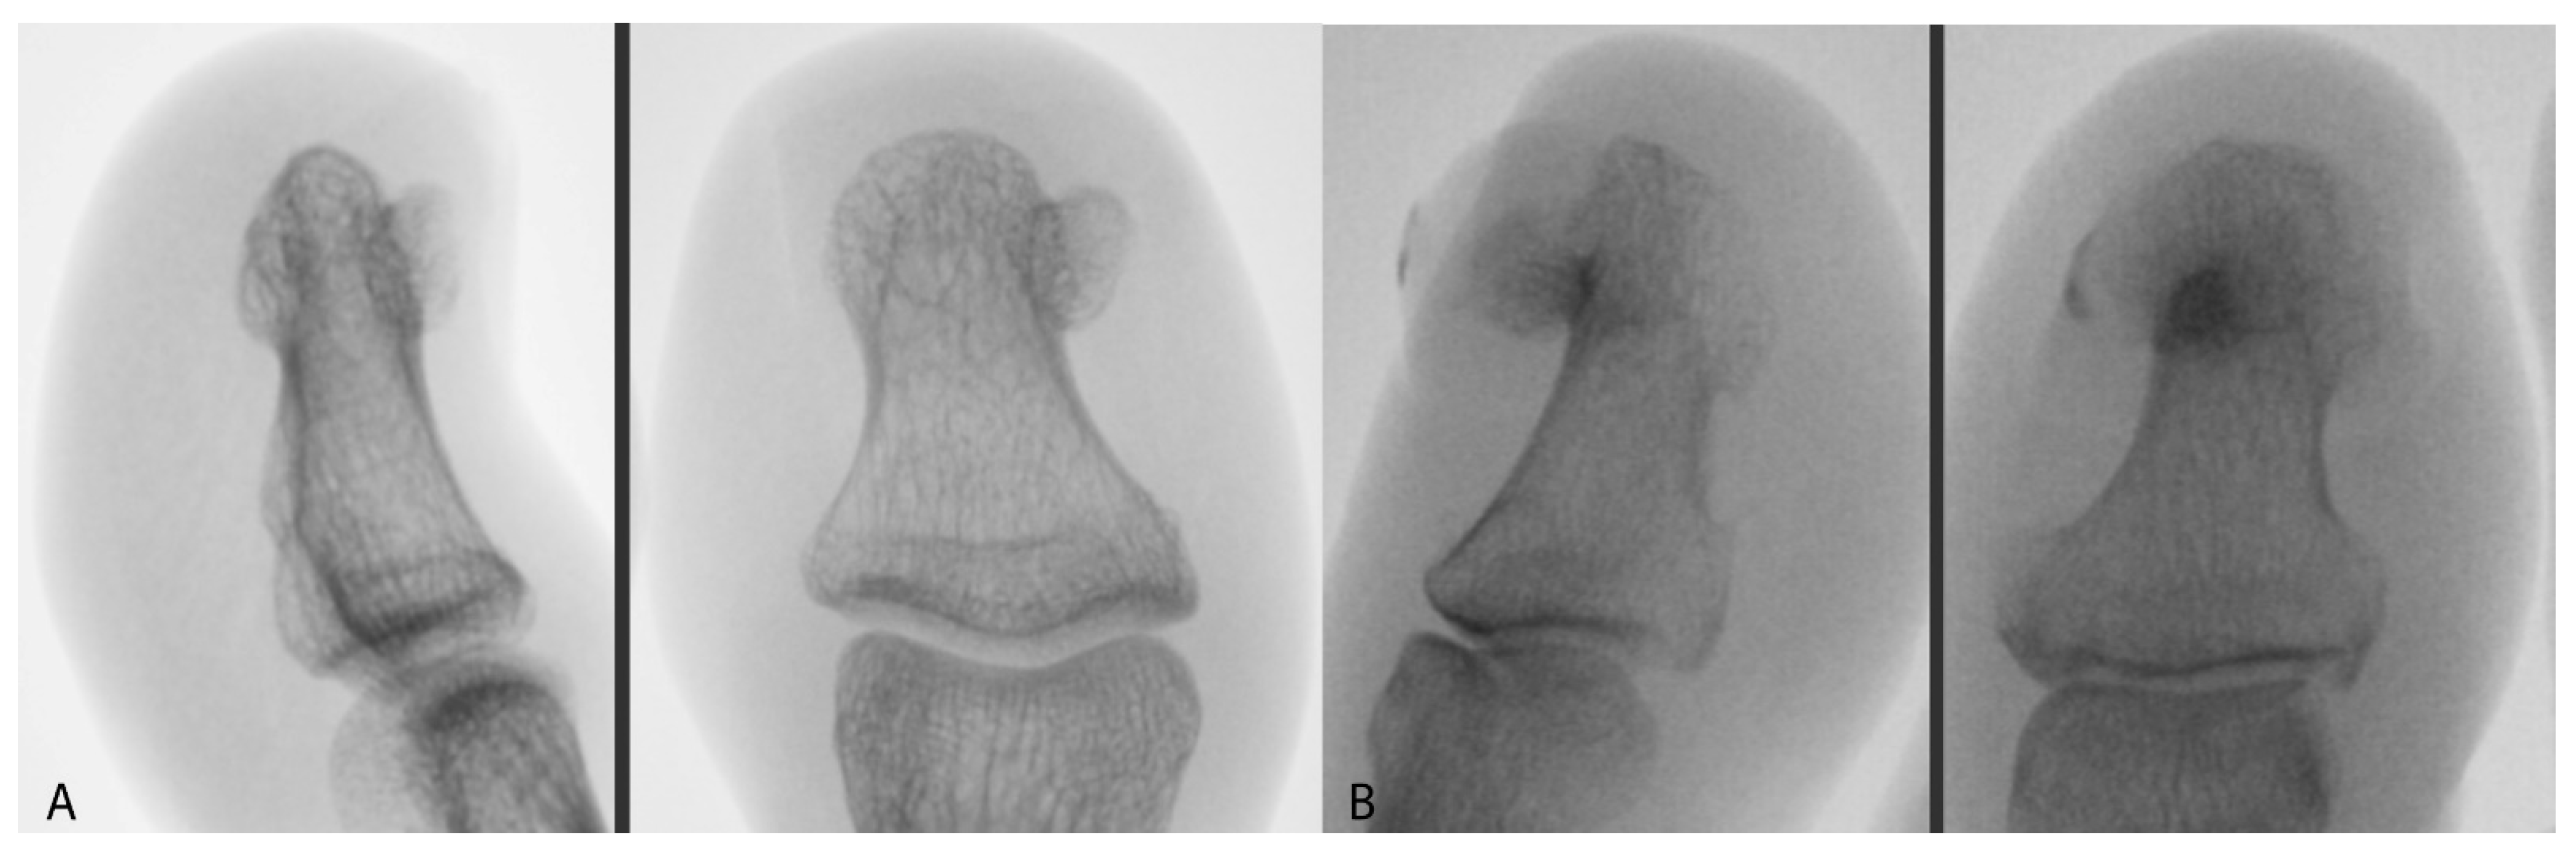

In order to qualify for surgery, each patient received a health questionnaire, which was sent to the Healthy Foot Center along with photographs and X-rays (Figure 1). The patients received periprocedural recommendations: an inventory of dressing materials, a method of preparing the toe for surgery, as well as postoperative procedures, including instructions for changing the dressing. They also received recommendations that, for three consecutive days before the procedure, the toe should be soaked for 10 min in a prepared solution of potassium permanganate and then dried and lightly bandaged. On the day of the surgery, the patient reported with the toe secured by a bandage.

Figure 1.

AP and lateral X-ray image of (A) SO and (B) SE.